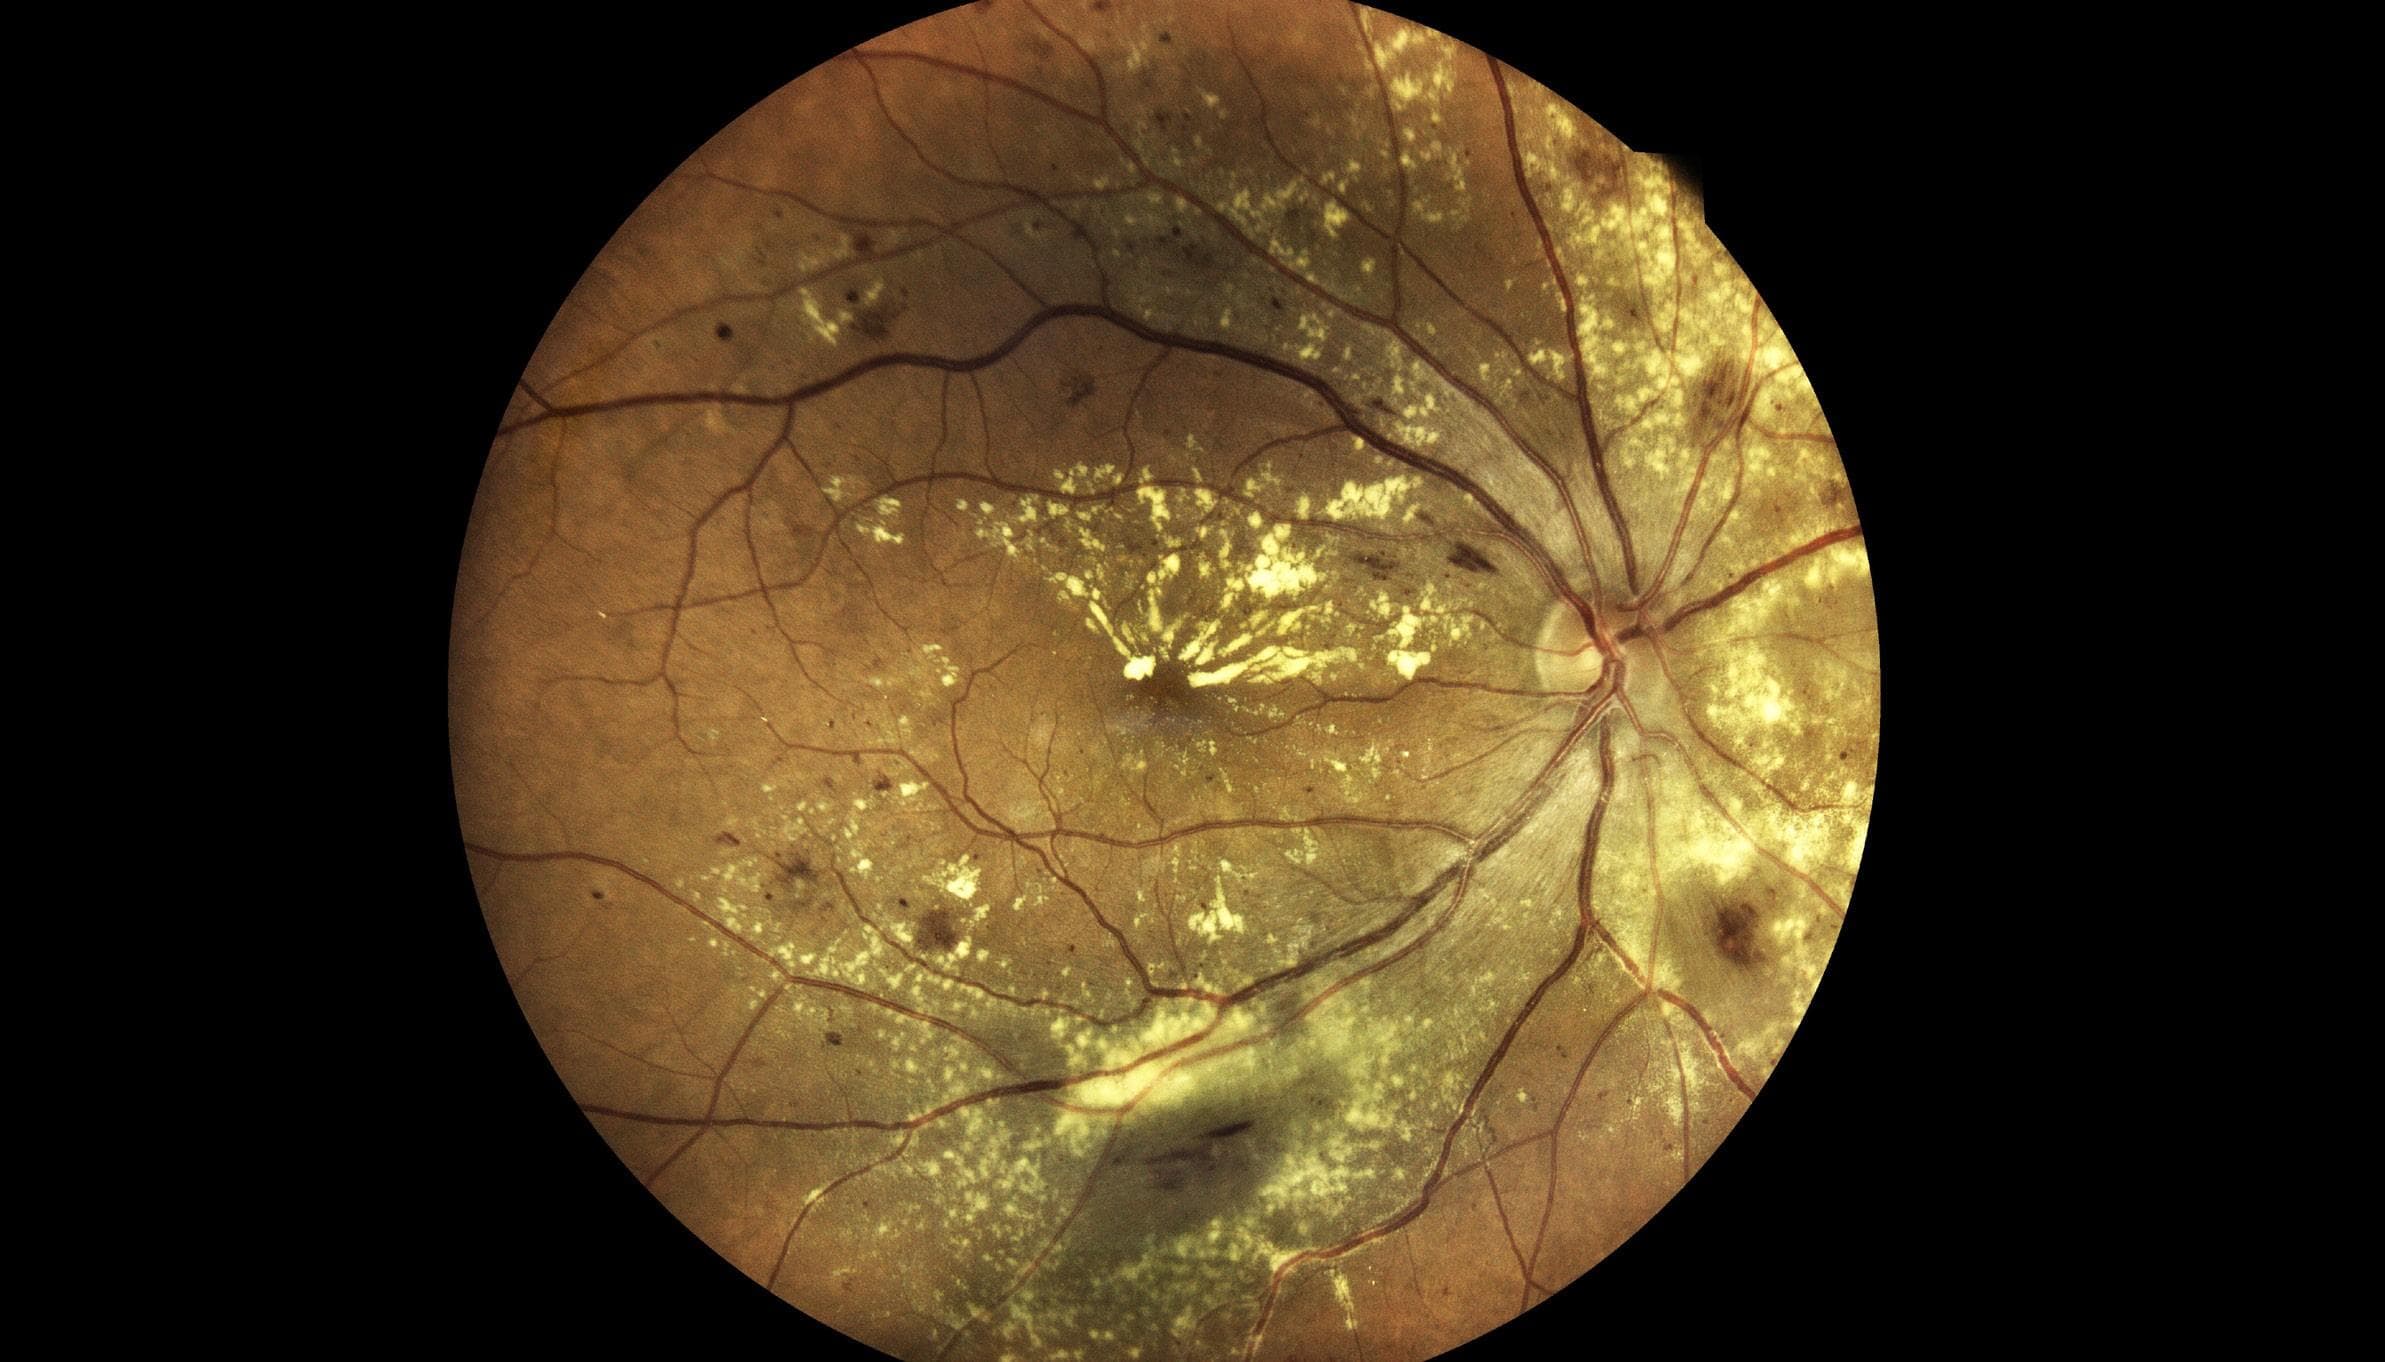

Epiretinal Membranes Looking Beyond the Macula

Epiretinal membranes (ERMs) are a common finding within optometric practice, with some studies reporting a prevalence of up to 34%. While many clinicians may consider an ERM a relatively benign finding, it is important to recognise that they can be associated with a plethora of vision-threatening ocular disorders